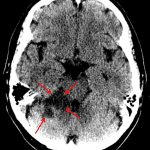

- Areas of hypoattenuation in the right middle cerebellar peduncle and superior cerebellum with loss of gray-white differentiation

- Local mass effect partially effaces the right ambient cistern

- Patchy hypoattenuation in the left posterior periventricular white matter

- Superior cerebellar artery infarct

Areas of hypoattenuation in the right middle cerebellar peduncle and superior cerebellum with loss of gray-white differentiation are concerning for acute/subacute ischemia in the right superior cerebellar artery distribution. Associated edema with resultant partial effacement of the right ambient cistern. No evidence of hemorrhagic transformation, herniation, or hydrocephalus. Recommend brain MRI for further evaluation.

Patchy hypoattenuation in the left posterior periventricular white matter represents age-indeterminate ischemia.